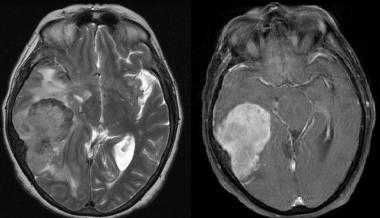

![image009]()

![image011]()

Метастазы головного мозга на МРТ. Фото. Определяются множественные метастазы в мозг при раке легкого: слева в режиме Т1-ВИ в виде гипоинтенсивных образований, справа — в режиме Т2-ВИ виде множественных участков повышенного сигнала, окруженных зоной перифокального отека. У пациента подтверждена первичная опухоль легкого.